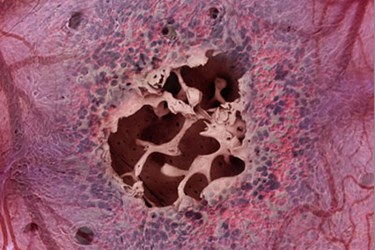

To create the bone marrow-on-a-chip device, researchers filled a circular chip approximately the size of a coin battery with dried bone powder. They then implanted the chip under the skin of a living mouse and left it there for eight weeks. At the end of the eight weeks, the chip was surgically removed and examined under a microscope.

Researchers found that the surgically implanted circular chip had developed into a ring-shaped bone, and the bone marrow found within the fabricated structure was functioning just like natural bone marrow, mirroring natural blood cell production. .

Image Credit: James Weaver, Harvard’s Wyss Institute